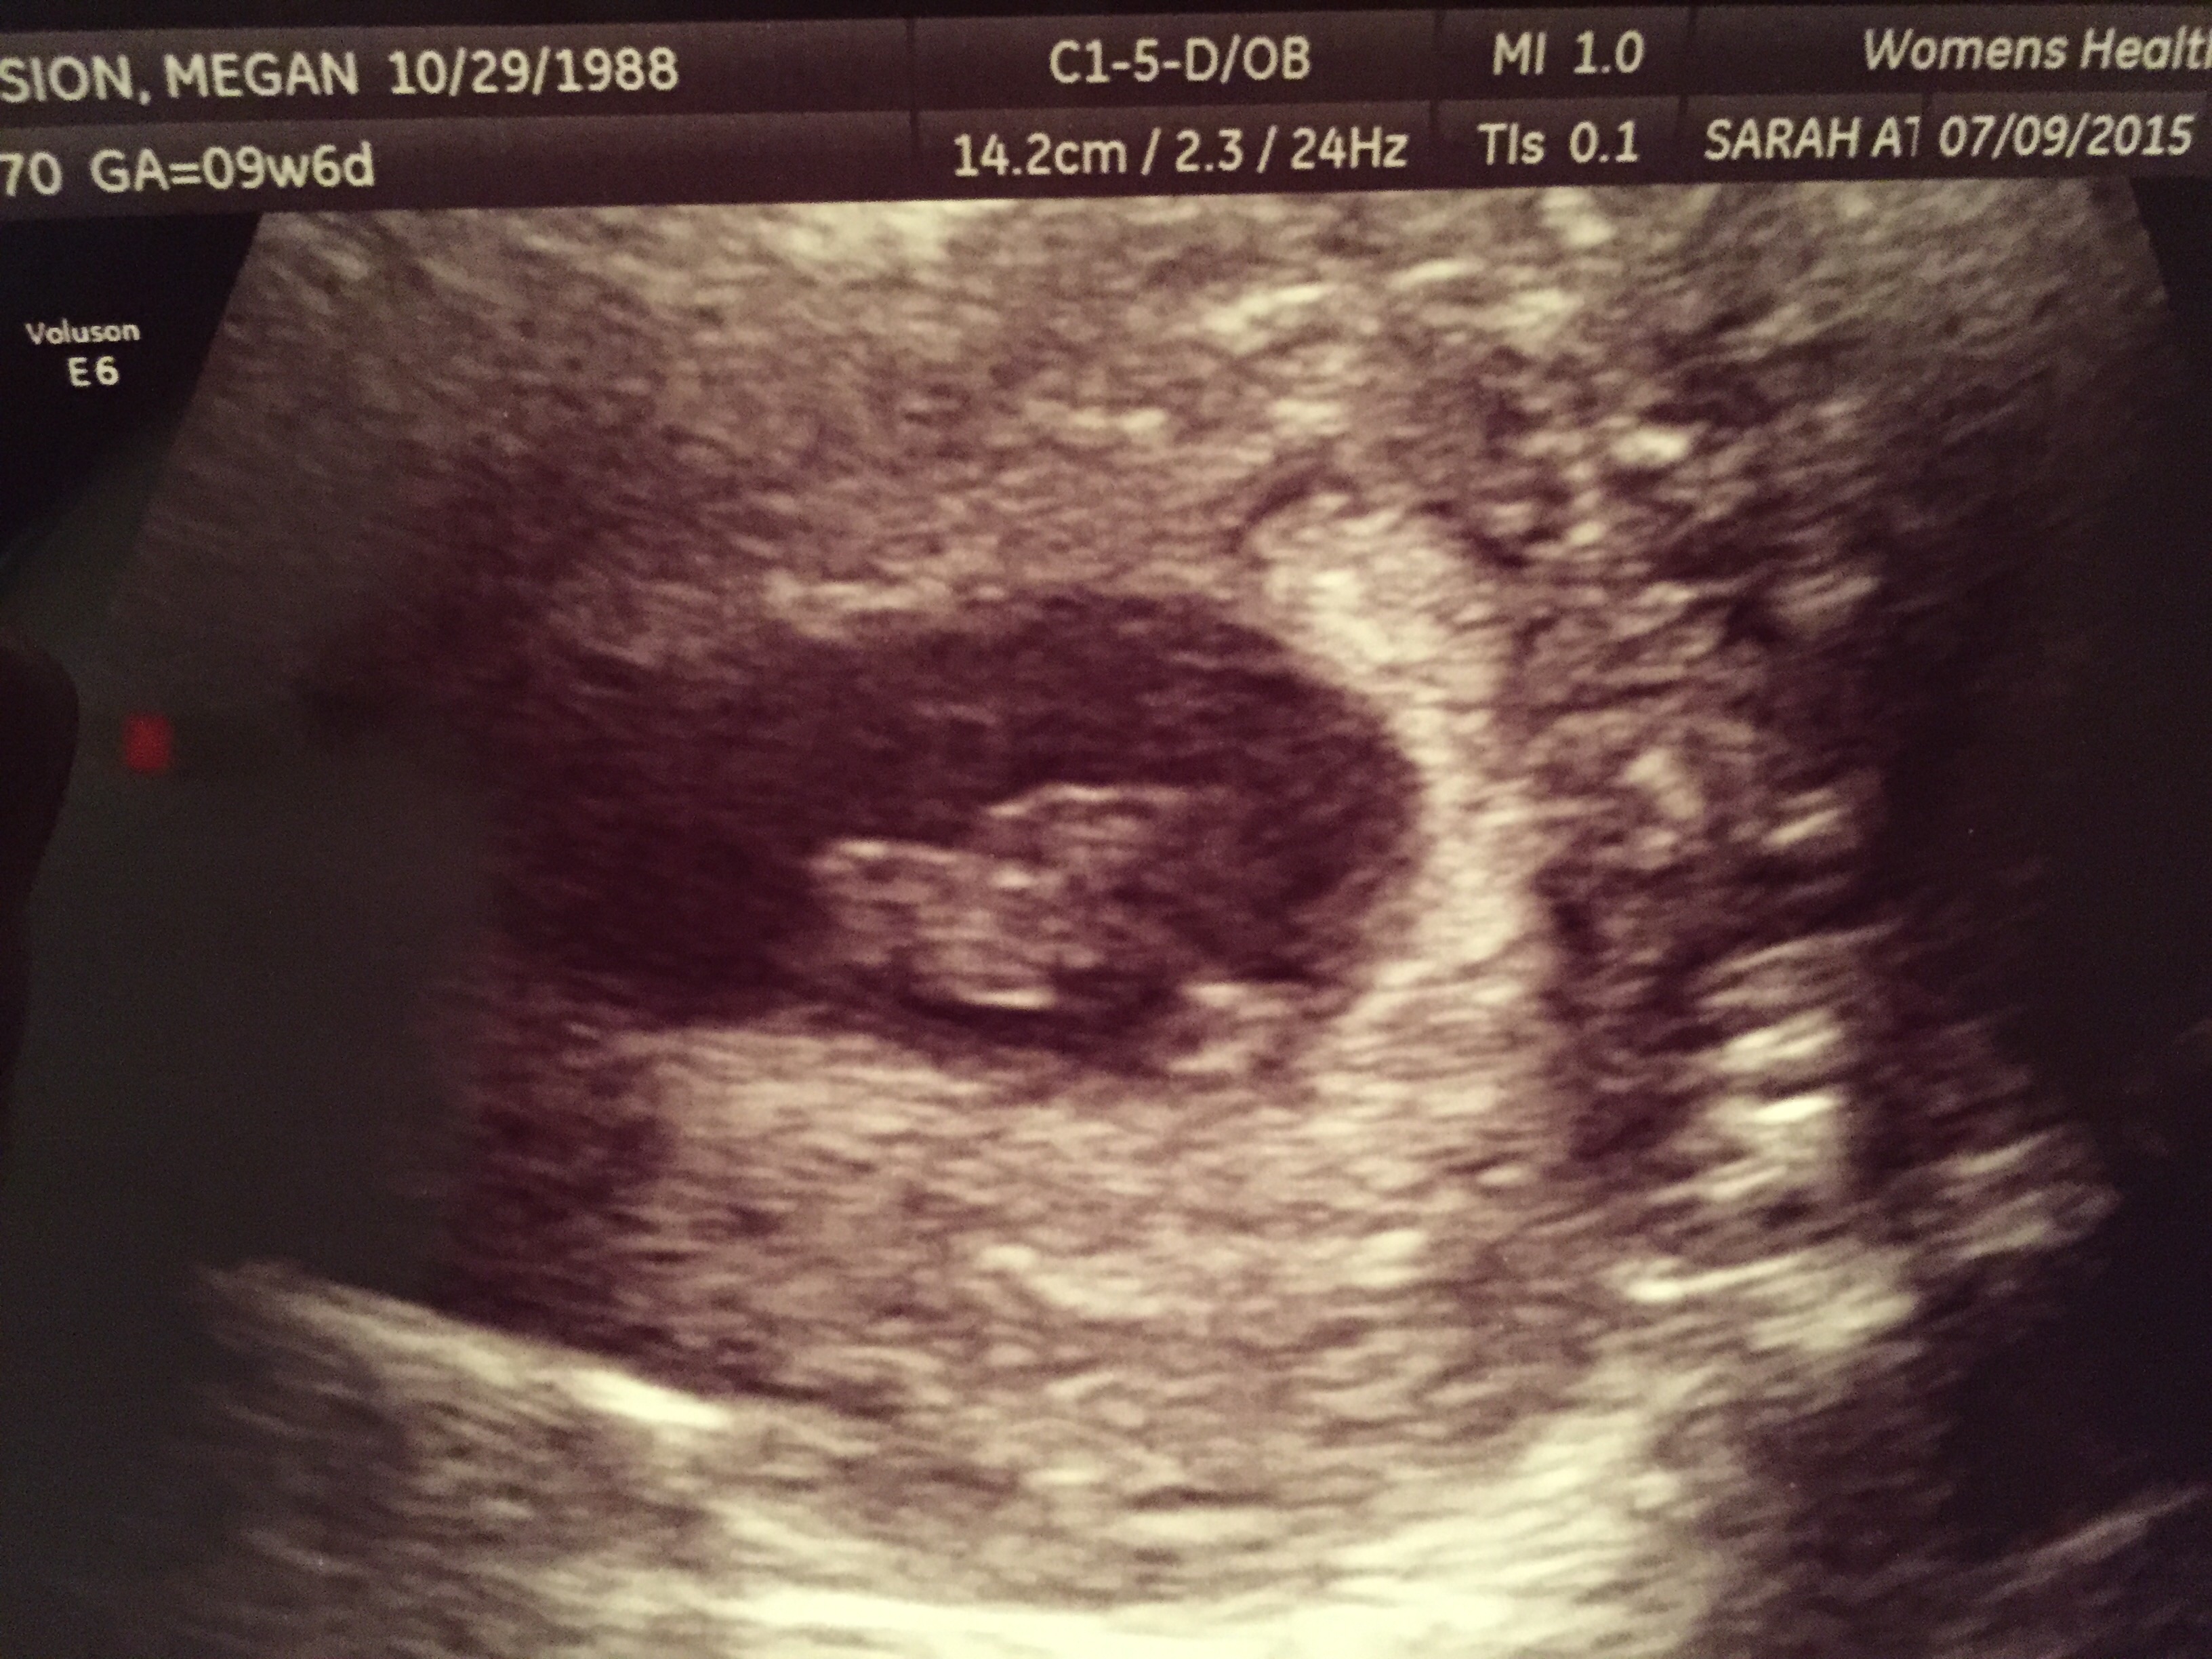

Got a great pic of our baby at 9w6d yesterday! Baby was verrrryy squirmy and was moving around. It was amazing to see baby active! Heart rate was 167 but she said that it was probably high because baby was moving so much! Due date February 24th.